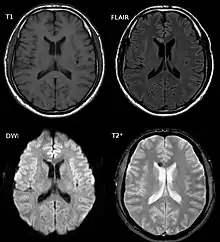

Diffuse axonal injury after a motorcycle accident. MRI after 3 days: on T1-weighted images the injury is barely visible. On the FLAIR, DWI and T2*-weighted images a small bleed is identifiable.

DAI is difficult to detect since it does not show up well on CT scans or with other macroscopic imaging techniques, though it shows up microscopically.[9] However, there are characteristics typical of DAI that may or may not show up on a CT scan. Diffuse injury has more microscopic injury than macroscopic injury and is difficult to detect with CT and MRI, but its presence can be inferred when small bleeds are visible in the corpus callosum or the cerebral cortex.[34] MRI is more useful than CT for detecting characteristics of diffuse axonal injury in the subacute and chronic time frames.[35] Newer studies such as Diffusion Tensor Imaging are able to demonstrate the degree of white matter fiber tract injury even when the standard MRI is negative. Since axonal damage in DAI is largely a result of secondary biochemical cascades, it has a delayed onset, so a person with DAI who initially appears well may deteriorate later. Thus injury is frequently more severe than is realized, and medical professionals should suspect DAI in any patients whose CT scans appear normal but who have symptoms like unconsciousness.[9]